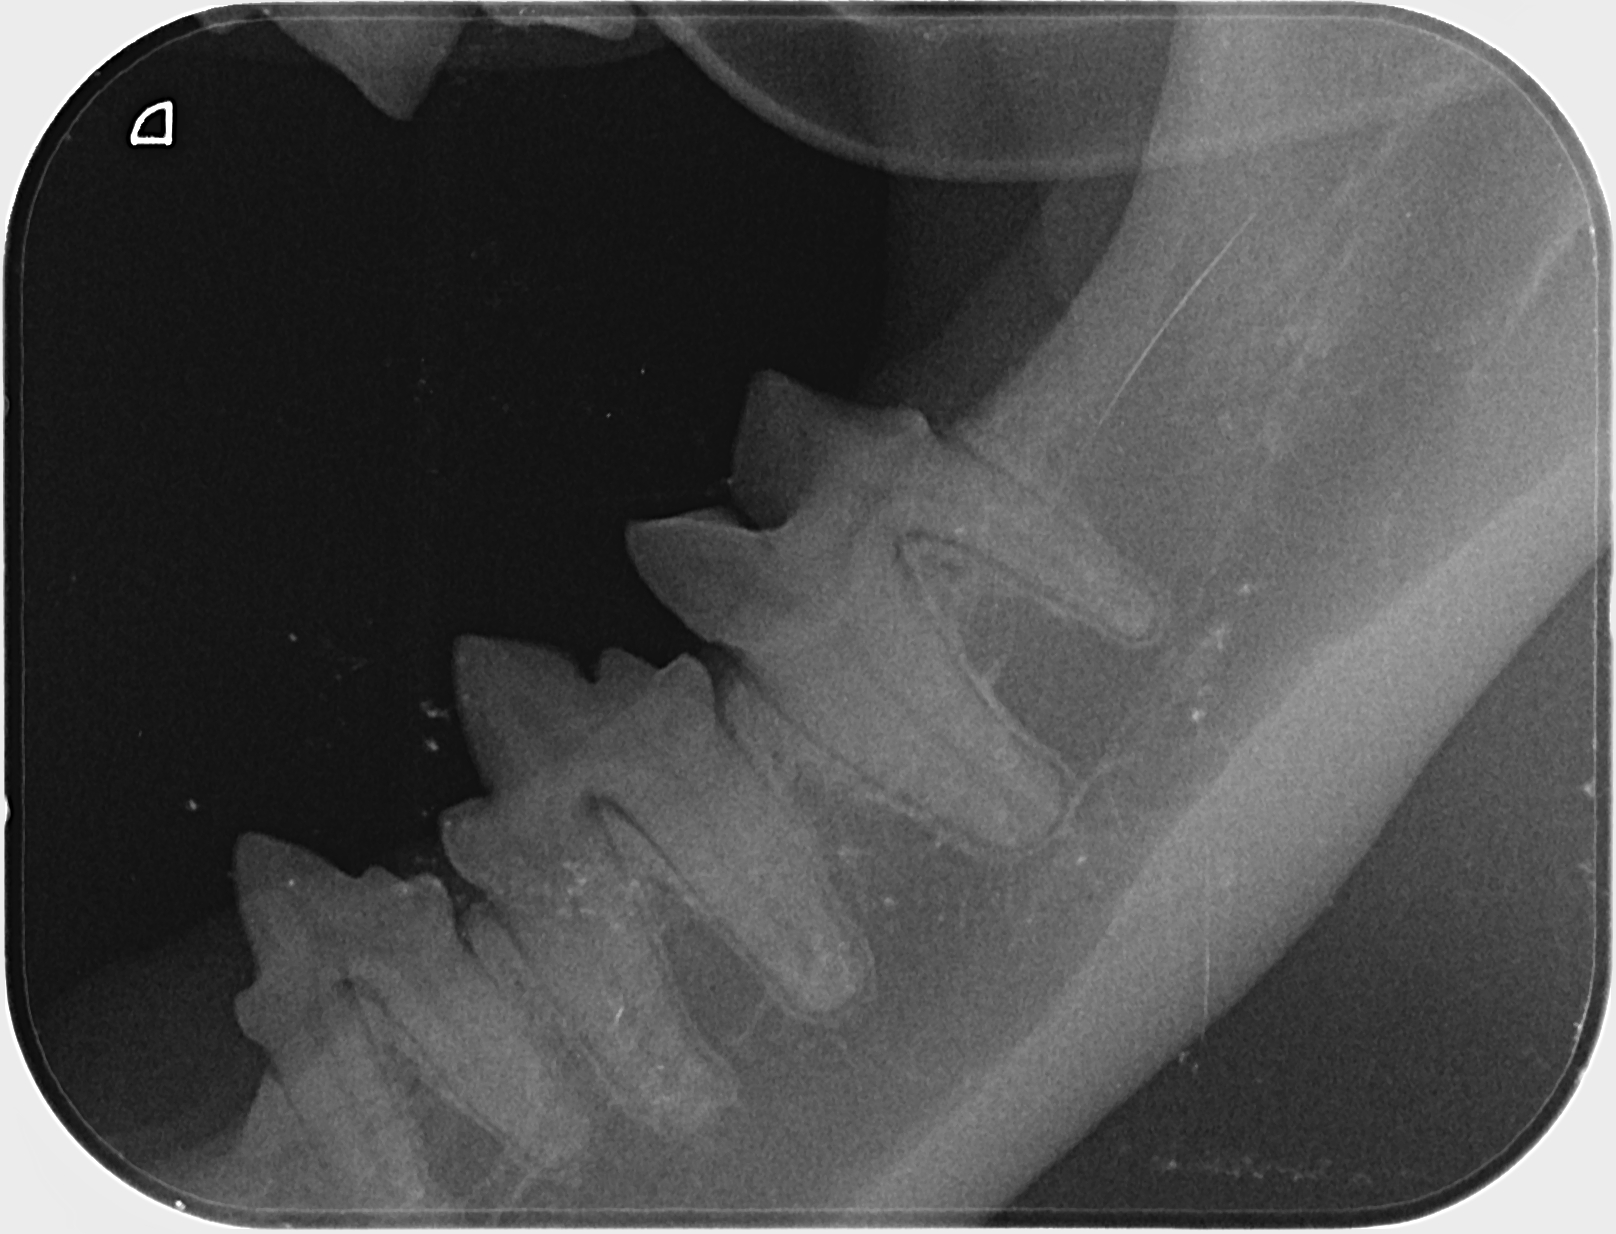

Kissan hampaat voivat näyttää päällisin puolin ihan hyvältä, mutta hampaiden juurissa voi olla piileviä ongelmia. Ainoa tapa selvittää, ovatko hampaat oikeasti kunnossa, on ottaa hammasröntgen.

IC Moggi Sikuri Sakari(Kilju) piipahti jo jonkin aikaaa sitten Amyvetissä hammahuollossa ja samassa kalusto pääsi kuviin. Tulos oli juuriaan myöten terveet hampaat. Hammaskiven poistoa pienesti ja ohjeeksi harjailla hampaita ahkerasti.

Ohessa muutama kuva malliksi.